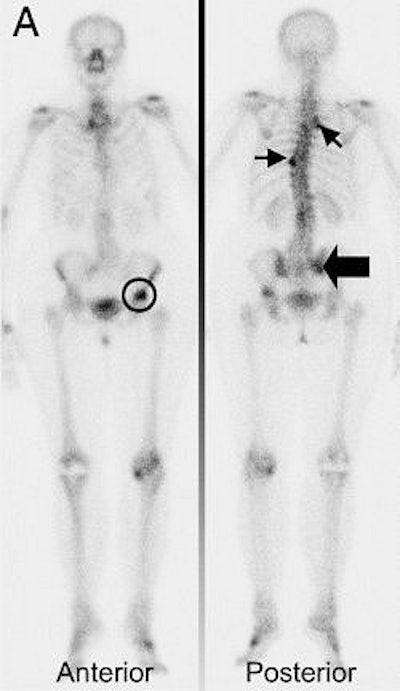

![]() |

| Seventy-four-year-old woman, under tamoxifen treatment, presented with positive bone scan showing multiple lesions in vertebral spine T3 and ribs, T9 (small arrows), right sacroiliac region (thick arrow), and left femur (circle). |